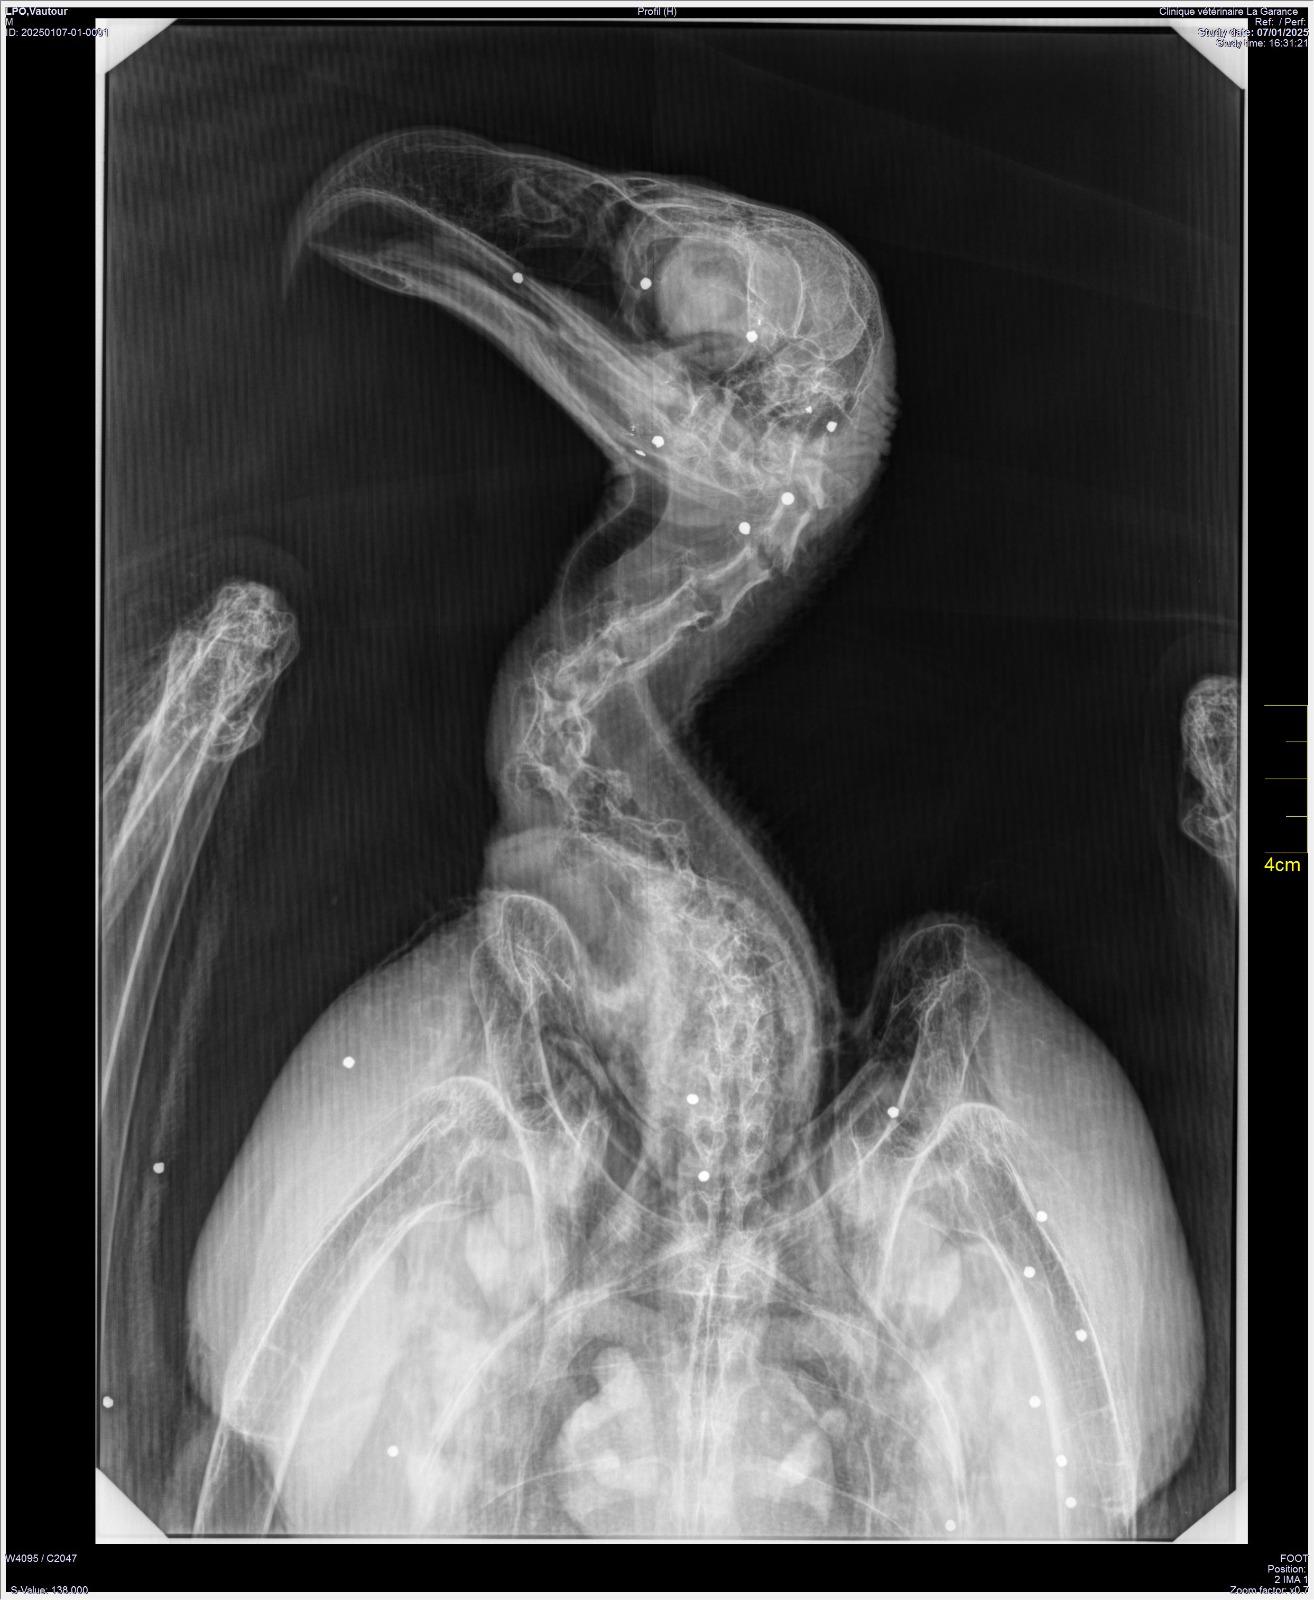

Au début du mois de janvier, nous avons accueilli un Vautour moine en détresse, une espèce très menacée en France. Trouvé gisant au bord d’une rivière dans les Alpes de Haute Provence, le grand rapace est arrivé extrêmement affaibli au Centre de sauvegarde. Victime d’une importante hémorragie interne, il ne pouvait pas prendre appui sur sa patte gauche et avait un œil injecté de sang. Une radiographie a révélé la cause de ces maux, mais aussi la gravité de son état : son corps était criblé de plombs. Aucune partie n’avait été épargnée : tête, ailes, corps, pattes. Au total plus d’une soixantaine de plombs, ce qui laisse supposer un tir à proximité.

ILD est restée en soins intensifs pendant plusieurs semaines. Elle a subi une opération pour lui retirer le plus gros plomb dans l’aile, réalisée par le Dr Frank Dupraz, notre vétérinaire référent, qui nous a aussi fourni des conseils tout au long de sa convalescence et que nous remercions chaleureusement.